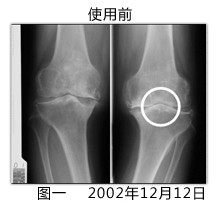

本剤は現時点で根本的な治療法のない変形性関節症、慢性関節リウマチ、また椎間板の異常による椎間板ヘルニアに対しての鎮痛効果を期待したサプリメントであると考えられ、薬 理作用、機序を解明しなければなりません。また、レントゲン上で膝、股関節、腰椎ともに、再生は認められた。

(中文翻译:)百傲鲨软骨粉是针对目前没有根本疗法的退行性关节炎、类风湿 性关节炎和椎间盘突出等症状具有止痛效果的食疗用品,其药理作用必须得到解明。另,通过X片确认到了膝盖、髋关节、腰椎等软骨再生。